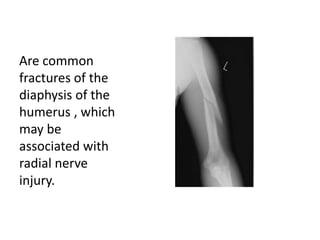

Are common

fractures of the

diaphysis of the

humerus , which

may be

associated with

radial nerve

injury.